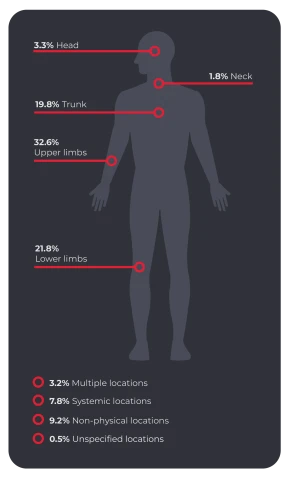

The bodily locations of serious claims (involving more than one week or working time lost) according to Safe Work Australia for the same time period notes that the upper limbs are the site of most injuries.